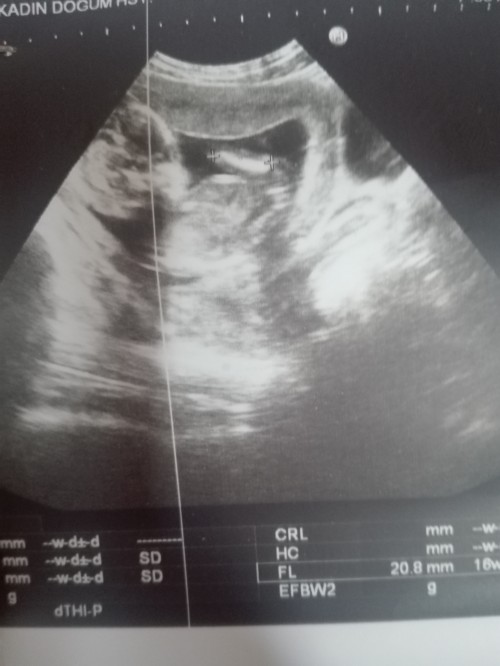

Sadece eğlencesine soruyorum lütfen yargılamayın bebeğim biraz inatçı galiba pozisyonu uygun değildi öğrenemedim sizce cinsiyet ne

imagebu kuzum iste

kac haftalik bu canim nub icin 11 12 13 haftalik olmasi gerek bu daha sekil almamis buyuk yanilma payiyla beraber kiz diyesim geldi ama nub a gore demiyorum nubu gorunmuyor cunku kizlar gec sekil alir ondan kiz diyorum

Vu 12 haftalık kuzum